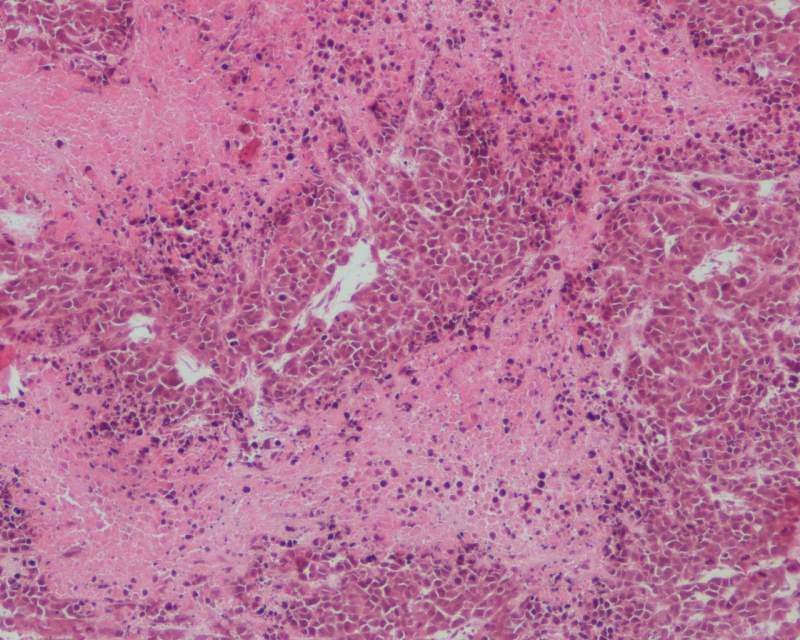

HE染色怎么判断细胞好坏死活

如题,怎么看好坏。

其次,这3个图的细胞怎么样,谢谢!

楼主,怎么感觉像出血的脏器啊?

是脾吗?

有点像血栓具体没看清楚,一片血海

不是

是肿瘤

这个让我怎么说呢,你看第三张图,正常细胞外间质你见过吧,你再看看这张,大量的红细胞渗出,放大的话我差点当成混合血栓。。不过出血肯定是有的